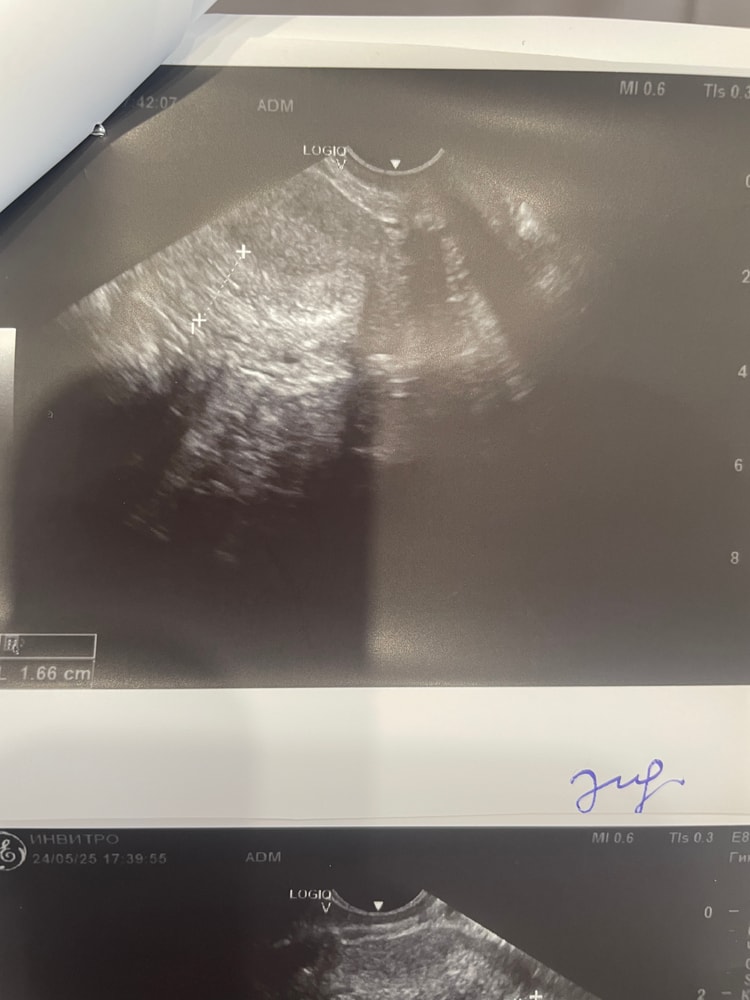

Девочки, узист написал нет дф, 15дц. Кто разбирается, посмотрите, пожалуйста, это просто фолликул крупный или все же доминантный?

Девчонки, если кому-то на узи поставят кисту с перегородкой, не спешите паниковать. На моем опыте: записываюсь на фолликулогенез. Узист описывает кисту с перегородкой, не описывает ее содержимое (платная известная клиника Тюмени). Я, прочитав что это такое, быстро расстроилась. Пришли м, после них иду на узи к врачу онкологу. Вердикт / фолликуля

За тот цикл киста увеличилась до 136 мл ( в районе 7 см). После М сдулась до 36 мл.

Сегодня 11 дц. Эндометрий 4 мм, в яичниках по 11-13 фолликулов, доминантного нет. Кто сталкивался? Мешает ли киста росту других фолликулов?